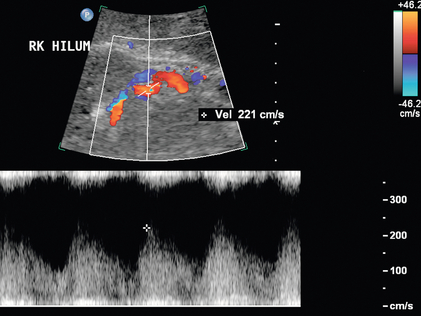

Для прямой спектральной допплеровской диагностики РАС были предложены различные критерии, что вызвало разногласия. PSV более 200 см/с ( рис. 9-12 ) был предложен для допплеровской диагностики уменьшения диаметра почечной артерии на 60%. В недавнем метаанализе PSV был лучшим критическим фактором в диагностике РАС с чувствительностью и специфичностью 85% и 92% соответственно. 29 Соотношение PSV почечной артерии и PSV аорты (RA/Ao) является еще одним критерием, предлагаемым для диагностики РАС. Соотношение RA/Ao PSV более 3,5:1 ( рис. 9-13 ) предполагает значительный уровень РАС, обеспечивая чувствительность 91% и специфичность 91%. Повышенное соотношение пиковой систолической скорости почечной артерии к систолической скорости дистальных почечных артерий также было предложено в качестве критерия диагностики РАС. Одно исследование 187 почечных артерий с ангиографической корреляцией также показало, что абсолютная почечная междолевая скорость PSV менее 15 см/с приводила к чувствительности и специфичности 87% и 91% соответственно для допплеровской диагностики 50% стеноза.Цзянь-Чу и др. недавно изучили влияние атеросклероза и возраста на параметры допплерографии для диагностики РАС и предполагают, что использование диагностических порогов почечно-аортального соотношения и почечно-междолевого соотношения различается у пациентов старше и моложе 46 лет. На другие сонографические критерии в их исследовании возраст пациентов существенно не влиял.

РИСУНОК 9-13. Стеноз почечной артерии. (А) Дуплексная допплерография почечной артерии демонстрирует пограничную пиковую систолическую скорость, 199 см/с. (B) Спектральная допплеровская волна аорты показывает, что максимальная скорость составляет 59 см/с. Рассчитанное отношение пиковой систолической скорости почечной артерии к аорте, равное 3,72, превышает порог 3,5, что указывает на значительный стеноз.